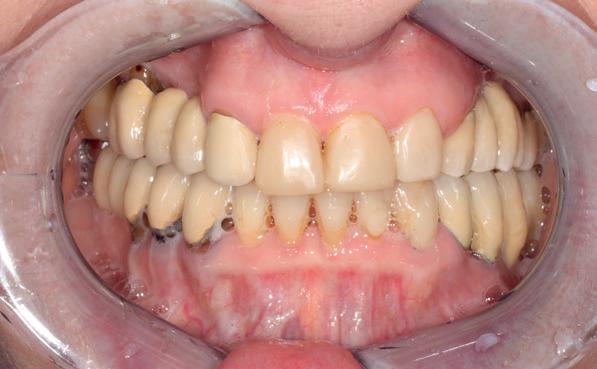

Een patiënt die conventioneel tandheelkundig vrijwel volledig is uitbehandeld, stelt de behandelaar voor complexe keuzes. In dit artikel wordt aan de hand van een uitgebreide casus beschreven hoe diagnostiek, prognosebepaling en interdisciplinair overleg leiden tot een voorspelbaar implantologisch behandeltraject. De casus illustreert hoe een ogenschijnlijk onsamenhangende restauratieve voorgeschiedenis kan uitmonden in een doordacht en succesvol full-arch implantaatgedragen rehabilitatieplan.

Op maandagochtend halfnegen dient zich in mijn agenda een nieuwe patiënt aan, mevrouw G. Ik heb haar nooit eerder gezien en een verwijzend tandarts, stuurt haar in met de vraag of ik met implantaten het eerste kwadrant wil restaureren aangezien daar de brug is losgekomen. Eerder heeft mevrouw G. een uitgebreide informed consent ontvangen met een gezondheidsvragenlijst. Er is verder intensief contact geweest met de verwijzer die ook enkele gemaakte röntgenfoto’s heeft gemaild. Tijdens het eerste onderzoek blijkt dat ze zich goed heeft ingelezen in alle informatie die haar per mail is toegestuurd. De patiënt is 65 jaar oud, spreekt moeilijk Nederlands, echter in het Engels kan ze zich goed verstaanbaar maken. Bij navraag blijkt ze in verschillende landen te hebben gewoond in verband met de werkzaamheden van haar man. Ze is van een economisch hogere sociale klasse en woont nu sinds een jaar of vijf in Nederland. Ze is gezond en slikt geen medicijnen, behalve pijnstillers tegen de pijn in haar gebit.

landen. Ze heeft zich uitgebreid laten behandelen met kroon- en brugwerk. Haar voornaamste klacht is van algemene en esthetische aard: haar gebit doet pijn bij functie en laat esthetisch te wensen over. Haar grootste wens is weer probleemloos te kunnen kauwen met een stevig, pijnvrij en gezond gebit.

Klinisch onderzoek en diagnostiek

Er worden lichtfoto’s gemaakt van het gebit waarop blijkt dat enkel een aantal incisieven in boven- en onderkaak onbehandeld zijn (zie lichtfoto’s bij intake). De residentie lijkt vrijwel geheel gekroond en/ of overbrugd. Er is sprake van gedateerd kroon- en brugwerk waarbij kroonranden met de jaren bloot zijn komen te liggen en er is sprake van secondaire cariës. Daarnaast stel ik een fors verlies van verticale hoogte van de aanwezige processus in alle vier de kwadranten vast. Is hier sprake geweest van een verleden met ernstige parodontitis?

1. Gedateerd kroon- en brugwerk; fors aanhechtingsverlies zijdelingse elementen.

2. Ernstige parodontale afbraak verspreid aanwezig; (sec.)cariës

Op basis van de eerste indruk die ik krijg tijdens het globale klinische onderzoek, wordt een orthopantamogram (zie OPT bij intake) gemaakt. Samen met de meegestuurde röntgenopnames (zie solo’s) wordt eenvoudig vastgesteld dat er sprake is van ernstig botverlies, bijvoorbeeld bij de 16, 17 en de 18 tot 100% verlies aan alveolair bot. De 16 vertoont daarnaast een grote peri-apicale laesie. In het eerste kwadrant lijkt daarom alleen de 12 een goede prognose te hebben. De 12 vormt samen met de 16 een vierdelige brug en deze constructie lijkt dus verloren. Overigens vermoed ik dat de 12 eigenlijk een cuspidaat is en ontbreekt de 12 (agenesie). Daarnaast worden sterk verdiepte ontstoken pockets geconstateerd bij de 16, 17 tot 12 mm en zijn de elementen sterk verhoogd mobiel. De 11 lijkt als enige element van de gehele dentitie niet te zijn behandeld.

In het tweede kwadrant ziet de situatie er in eerste instantie röntgenologisch veel beter uit. Een vierdelige brug rust op twee pijlers: de 24—27. Ook hier is sprake van vermoedelijk agenesie van de 22. Bij nader onderzoek blijkt diepe cariës onder de kroon